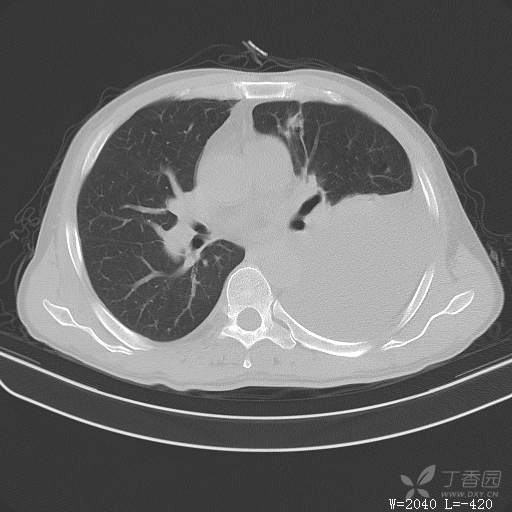

这个胸腔积液原因不寻常,大家猜猜看(得细心,这个很有意思)(俱乐部3)

简要病史:胸闷、憋气伴低热1月

体格检查:T:37.6℃;P:92次/分;R:20次/分;Bp:100/60mmHg,神清,呼吸平稳,周身未触及肿大淋巴结,右肺及左上肺叩诊清音,左下肺叩诊浊音,右肺及左上肺呼吸音粗,左下肺未闻及呼吸音,心率92次/分,律齐,无杂音。腹部平坦,软,全腹无压痛,无反跳痛及肌紧张,肝脾肋下未触及,双下肢无水肿。

辅助检查:白细胞数目4.41 × 10^9/L,中性粒细胞百分比82.1%,*血红蛋白111g/L,*血小板数目91 × 10^9/L,凝血四项:凝血酶原时间12.5秒,国际标准化比值1.07,活化部分凝血酶原时间36.1秒,纤维蛋白原浓度6.52g/L,肾功能示:肌酐47.4umol/L,尿酸150umol/L,电解质示:钠133.5mmol/L,D-二聚体0.88mg/L,血沉67.71MM/H,C-反应蛋白114.6mg/L,肝功能:*总蛋白49.6g/L,*白蛋白27.4g/L,查胸水常规及胸水生化提示渗出液,胸水ADA154U/L,查胸水病理未见肿瘤细胞。超声:腹膜后有3~4枚肿大淋巴结,直径1~1.5厘米,余浅表淋巴结不大。

临床诊断:左侧胸腔积液

治疗经过:胸水引流。胸水白蛋白23.8克/升,乳酸脱氢酶275单位/升,胸苷激酶182单位/升,胸水外观黄色混浊,总细胞4320个/微升,白细胞4320个/微升,单核细胞80%,多核细胞20%。考虑结核性胸膜炎,结果查肿瘤标志物、胸水细胞学阴性,胸水TB—DNA阴性,结核菌素试验+,结核抗体阴性,TB-SPOT阴性,胸膜活检阴性。怎么办?